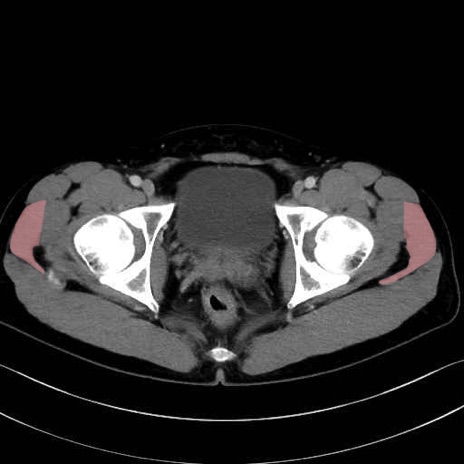

中殿筋 (Gluteus medius)